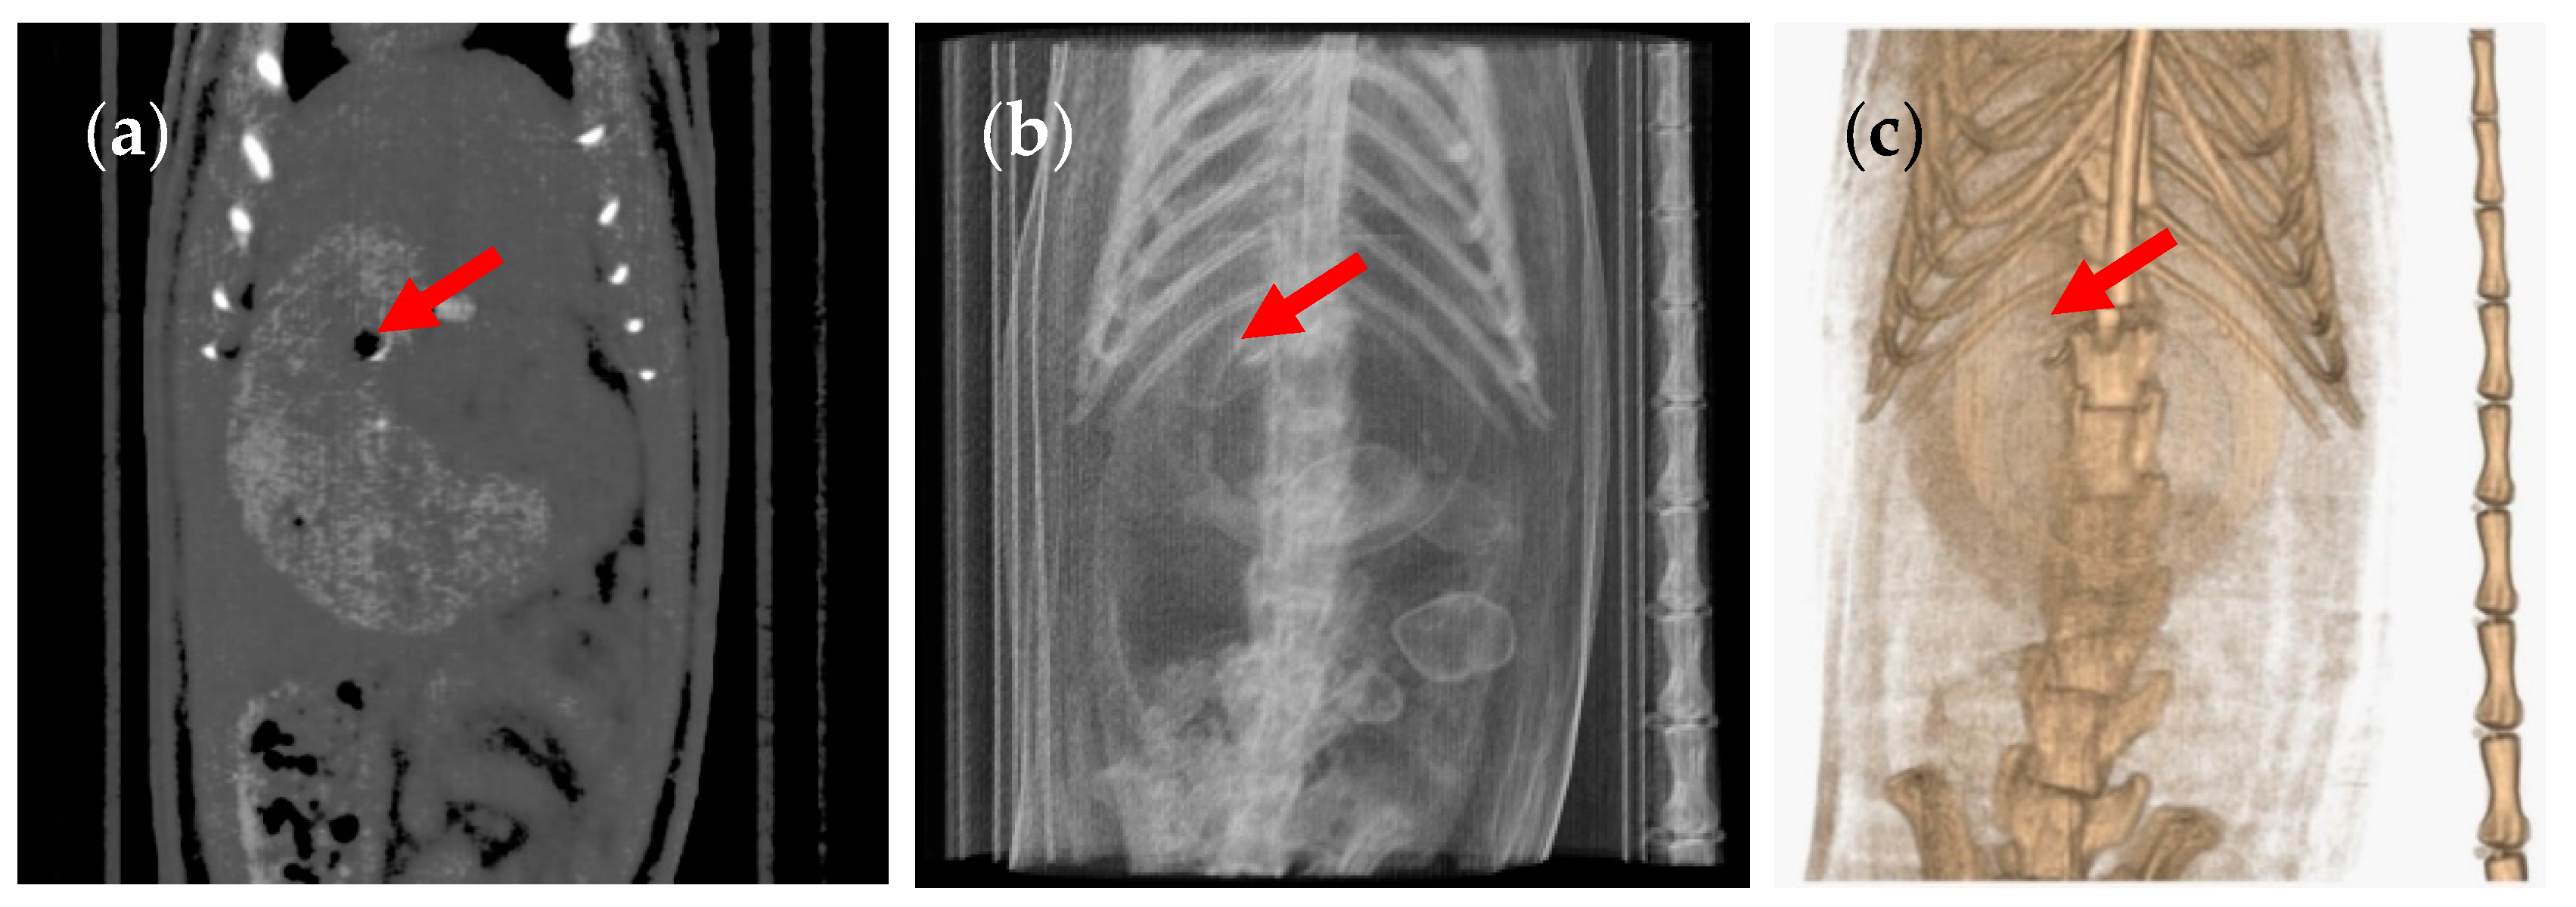

3. Results and Discussion